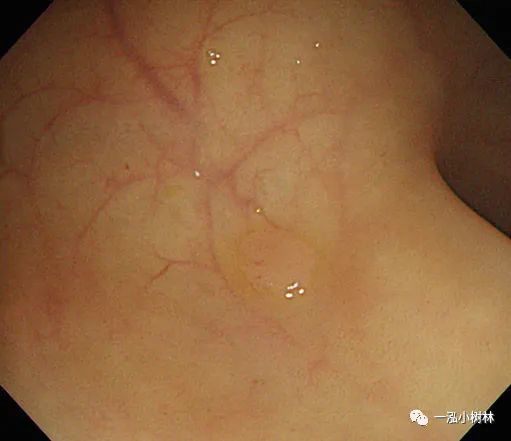

图1c 小息肉切除瘢痕,5年后腺瘤复发

图1d NBI观察